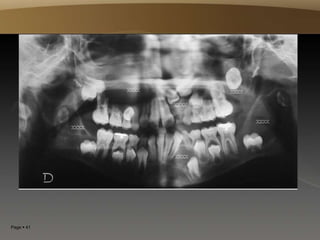

Page  41

Page  42